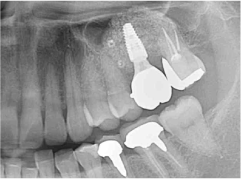

6か月経過後、再生した骨にインプラントを埋入しました。

その後、インプラントの上に被せ物をセットしました